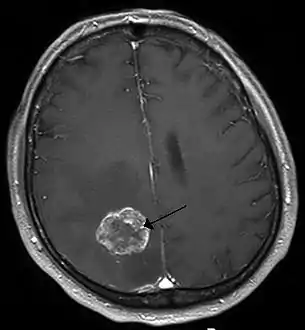

Imaging

Medical imaging plays a central role in the diagnosis of brain tumors. Early imaging methods – invasive and sometimes dangerous – such as pneumoencephalography and cerebral angiography have been abandoned in favor of non-invasive, high-resolution techniques, especially magnetic resonance imaging (MRI) and computed tomography (CT) scans, though MRI is typically the reference standard used.[37] Neoplasms will often show as differently colored masses (also referred to as processes) in CT or MRI results.

- Benign brain tumors often show up as hypodense (darker than brain tissue) mass lesions on CT scans. On MRI, they appear either hypodense or isointense (same intensity as brain tissue) on T1-weighted scans, or hyperintense (brighter than brain tissue) on T2-weighted MRI, although the appearance is variable.

- Contrast agent uptake, sometimes in characteristic patterns, can be demonstrated on either CT or MRI scans in most malignant primary and metastatic brain tumors.

- Pressure areas where the brain tissue has been compressed by a tumor also appear hyperintense on T2-weighted scans and might indicate the presence a diffuse neoplasm due to an unclear outline. Swelling around the tumor known as peritumoral edema can also show a similar result.

This is because these tumors disrupt the normal functioning of the BBB and lead to an increase in its permeability. More recently, advancements have been made to increase the utility of MRI in providing physiological data that can help to inform diagnosis and prognosis. Perfusion Weighted Imaging (PWI) and Diffusion Weighted Imaging (DWI) are two MRI techniques that reviews have been shown to be useful in classifying tumors by grade, which was not previously viable using only structural imaging.[38] However, these techniques cannot alone diagnose high- versus low-grade gliomas, and thus the definitive diagnosis of brain tumor should only be confirmed by histological examination of tumor tissue samples obtained either by means of brain biopsy or open surgery. The histological examination is essential for determining the appropriate treatment and the correct prognosis. This examination, performed by a pathologist, typically has three stages: interoperative examination of fresh tissue, preliminary microscopic examination of prepared tissues, and follow-up examination of prepared tissues after immunohistochemical staining or genetic analysis.